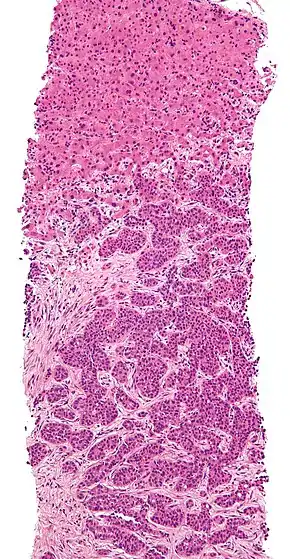

Cut surface of a liver showing multiple paler metastatic nodules originating from pancreatic cancer